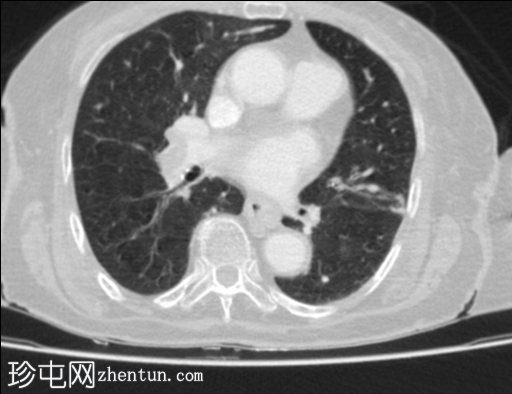

轴位肺窗

双侧肺动脉主干均可见大片充盈缺损,右侧上、下主干及左侧下叶主干可见闭塞

双肺清晰,可见肺叶少血,左上肺可见局灶性胸膜下条索状萎陷